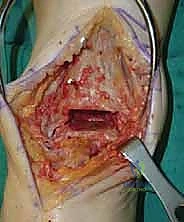

2. الشق الجراحي والنهج الأمامي (Incision & Anterior Approach)

يقوم الدكتور هطيف بعمل شق طولي دقيق في الجزء الأمامي من الكاحل، طوله حوالي 10-15 سم. يتم تشريح الأنسجة بعناية فائقة للوصول إلى المفصل.

* الحماية العصبية الوعائية: هذه هي الخطوة الأكثر حرجاً. يتم تحديد الحزمة الوعائية العصبية (الشريان الظنبوبي الأمامي والعصب الشظوي العميق) وسحبها برفق شديد لحمايتها من أي ضرر جراحي.

3. إزالة النتوءات العظمية وتحضير المفصل (Debridement)

بمجرد كشف المفصل، يقوم الجراح بإزالة الغشاء الزلالي الملتهب والزوائد العظمية (Osteophytes) التي تعيق الحركة. هذه الخطوة ضرورية لاستعادة المعالم التشريحية الطبيعية قبل إجراء القطع العظمي.